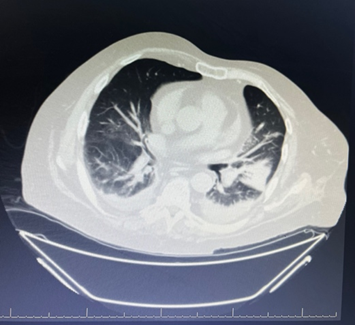

Fig 2: Findings suggest left lower lobe collapse-consolidation with air bronchograms (sparing the superior segment), associated with subsegmental atelectasis in the right basal lung and mild bilateral pleural effusion (left > right).

Figure 2